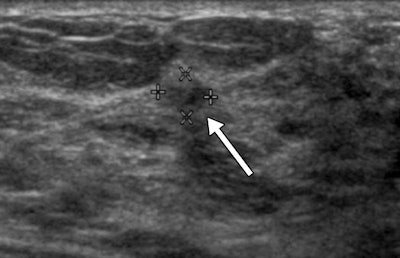

Sonograms show a BI-RADS category 3 lesion (arrow) in a 43-year-old woman. The lesion was described as 5-mm clustered microcysts at one-year follow-up (above). At two-year follow-up (below), the lesion had suspicious changes and was reclassified as a BI-RADS category 4A solid lesion. The lesion was not detected with mammography in either year. At biopsy, the lesion was determined to be an 18-mm invasive lobular cancer. Images courtesy of RSNA.

Out of 2,662 trial participants recruited between 2004 and 2006, 519 (19.5%) had 745 BI-RADS 3 lesions on ultrasound, representing 25% of all ultrasound-detected lesions in the study, according to the authors. Of these lesions, 124 (16.6%) were biopsied, and six of these biopsied lesions were malignant (representing 0.8% of BI-RADS 3 lesions). The average size of the detected cancers among the BI-RADS 3 lesions was 10 mm.

During follow-up imaging at six months, suspicious changes were observed in only one of the 745 lesions characterized as BI-RADS 3. At 12-month follow-up, suspicious changes were observed in a second BI-RADS 3 lesion, revealing an invasive breast cancer that had not yet spread beyond the breast.